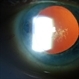

- Senile cataract (PAS x 16). Section shows liquefaction of the cortex under a deeply staining posterior capsule and a dense, lighter staining nuclear sclerosis. (Scheie Eye Institute, No. 4042.)